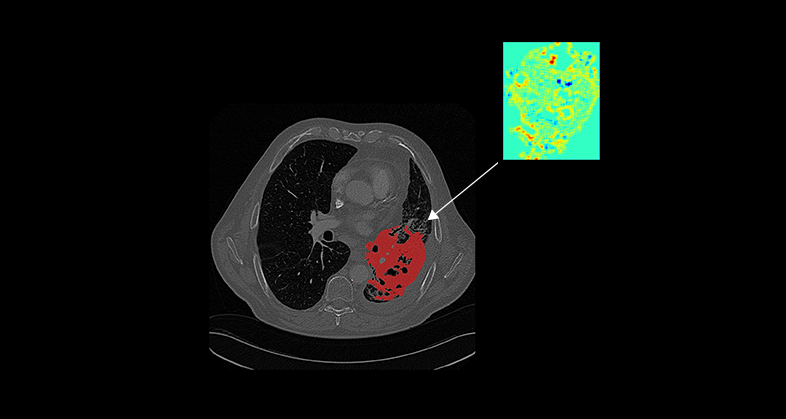

Our tissue-agnostic AI methods are applied at each stage of drug development programs. First we apply our AI techniques to harmonize image quality across hospitals and scanner models, then we perform automated organ and lesion detection. A tissue characterization follows to extract a signature based on the most relevant radiomics-based and deep features. These features are then used to develop predictive models of tumor growth, treatment response, overall survival, disease free survival, among many other patient outcomes.